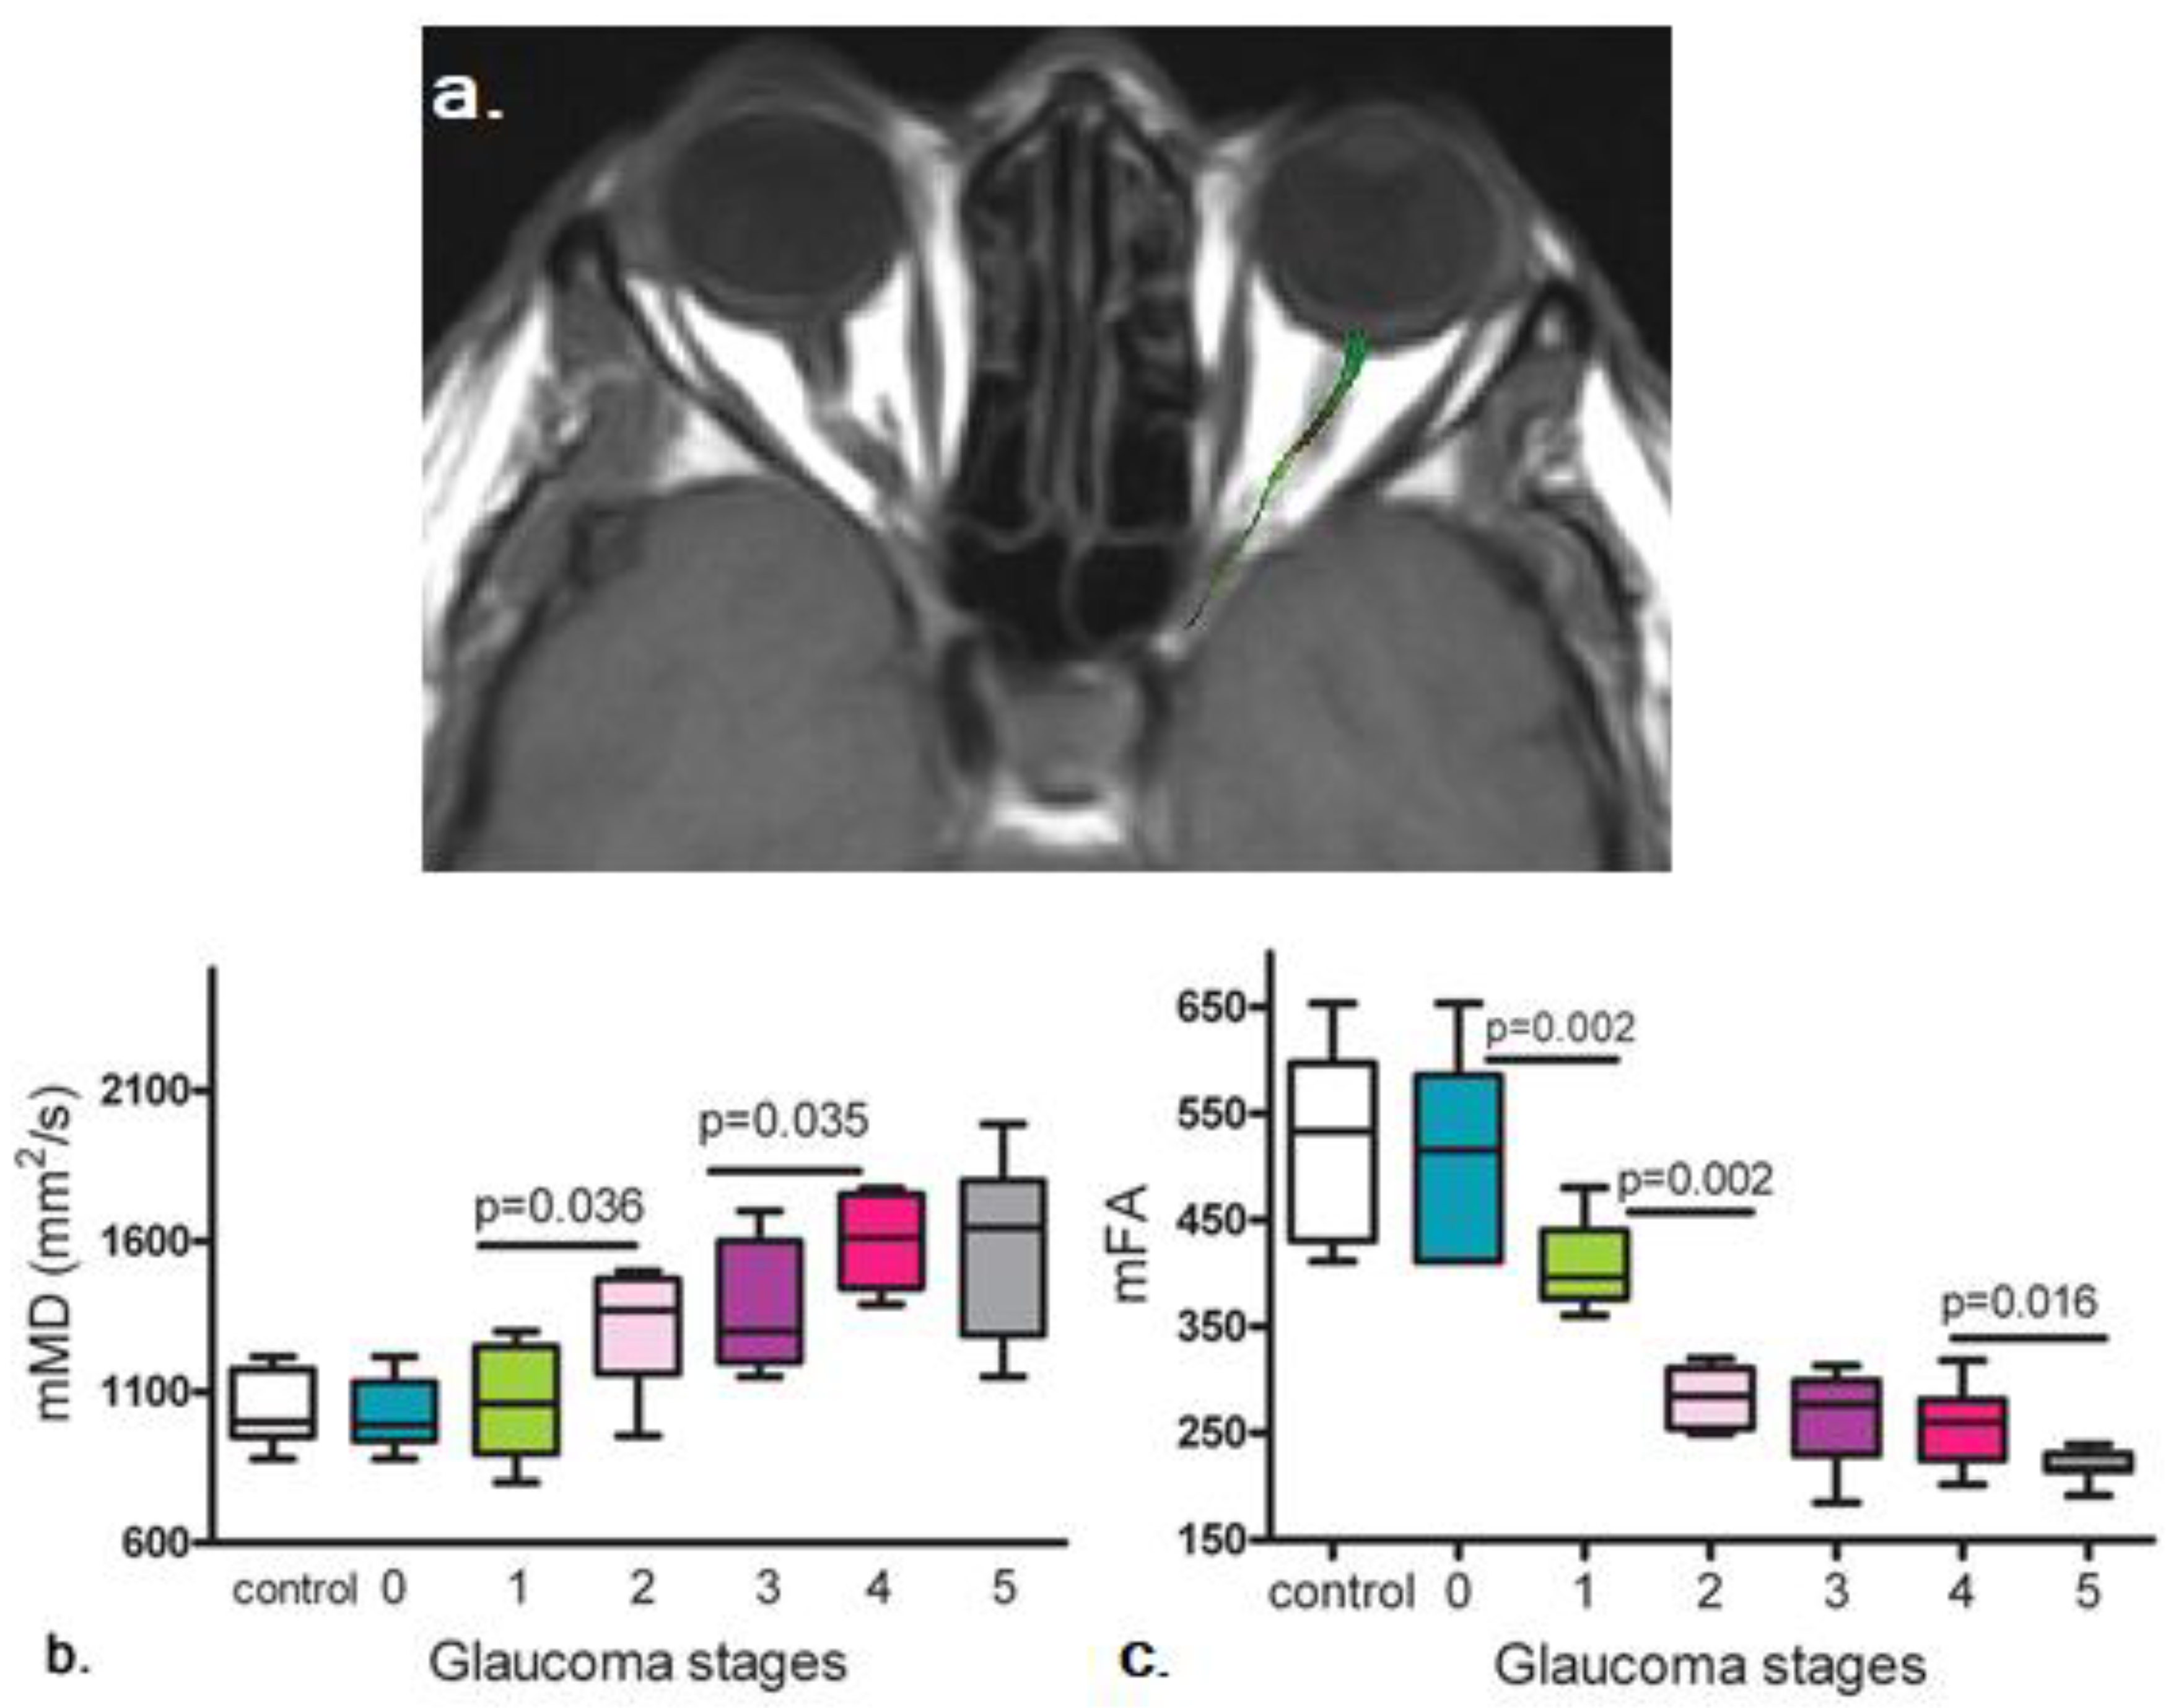

2.4. Diffusion Tensor Imaging (DTI) in Glaucoma

2.5. Diffusion Kurtosis Imaging (DKI) in Glaucoma